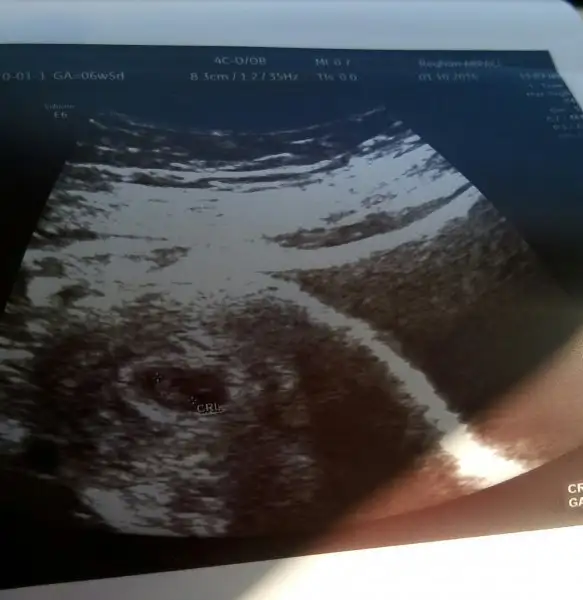

Hazirandaki gebeliğim sonlandı maalesef.pıhtılaşma olmuş ve bebeğimin kalbi durmuş.şimdi allahın izniyle tekrar hamileyim kan suşandırıcı iğne kullanıyyorum.yorum yaparmısınız usg lere.2 side karından .ilk resim 7 hafta 2.si 6+3.

Canim karindan ultrasyon sanirim burdaki teoriye gore kiz. Ama burdaki teori venimkinde tutmadi bende 6 haziranda dogum yaptim ve bebegim oglandi. Seninki benimkine cok benziyor